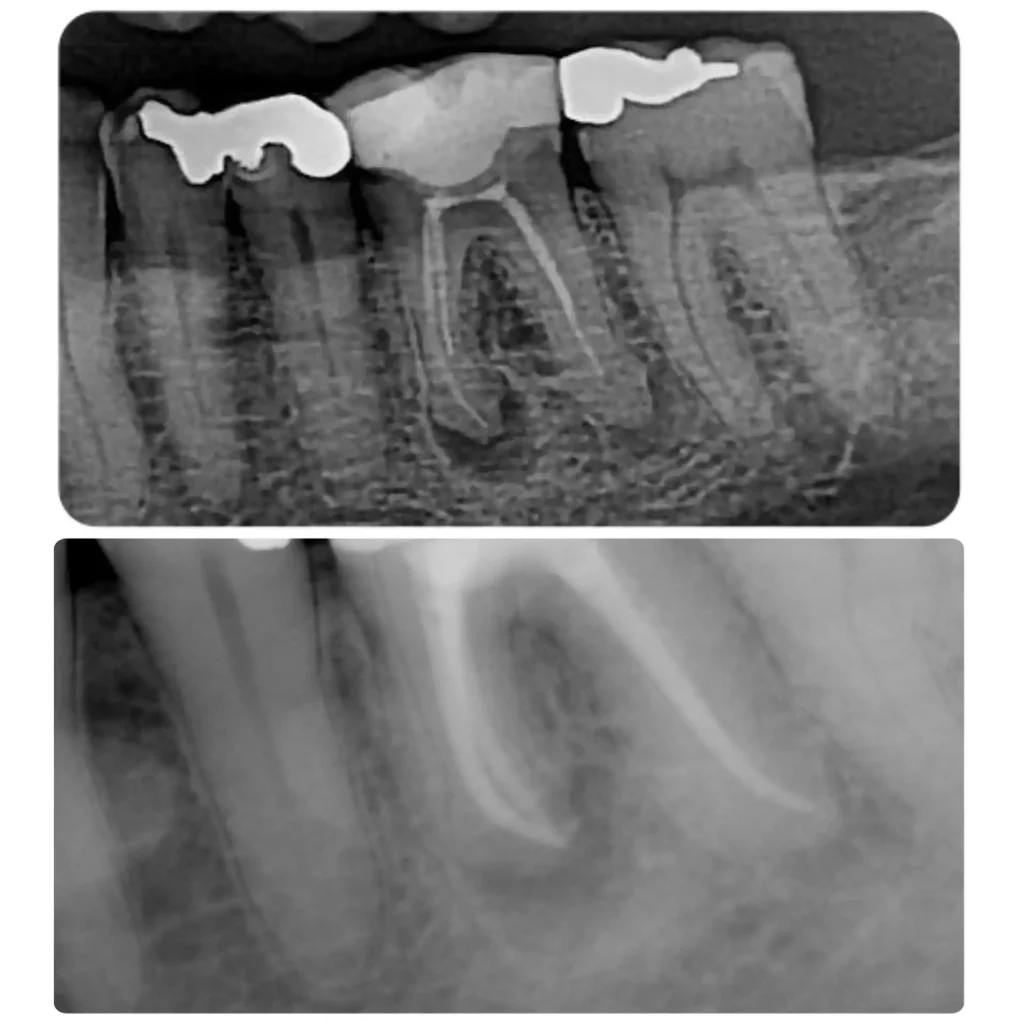

Case studies